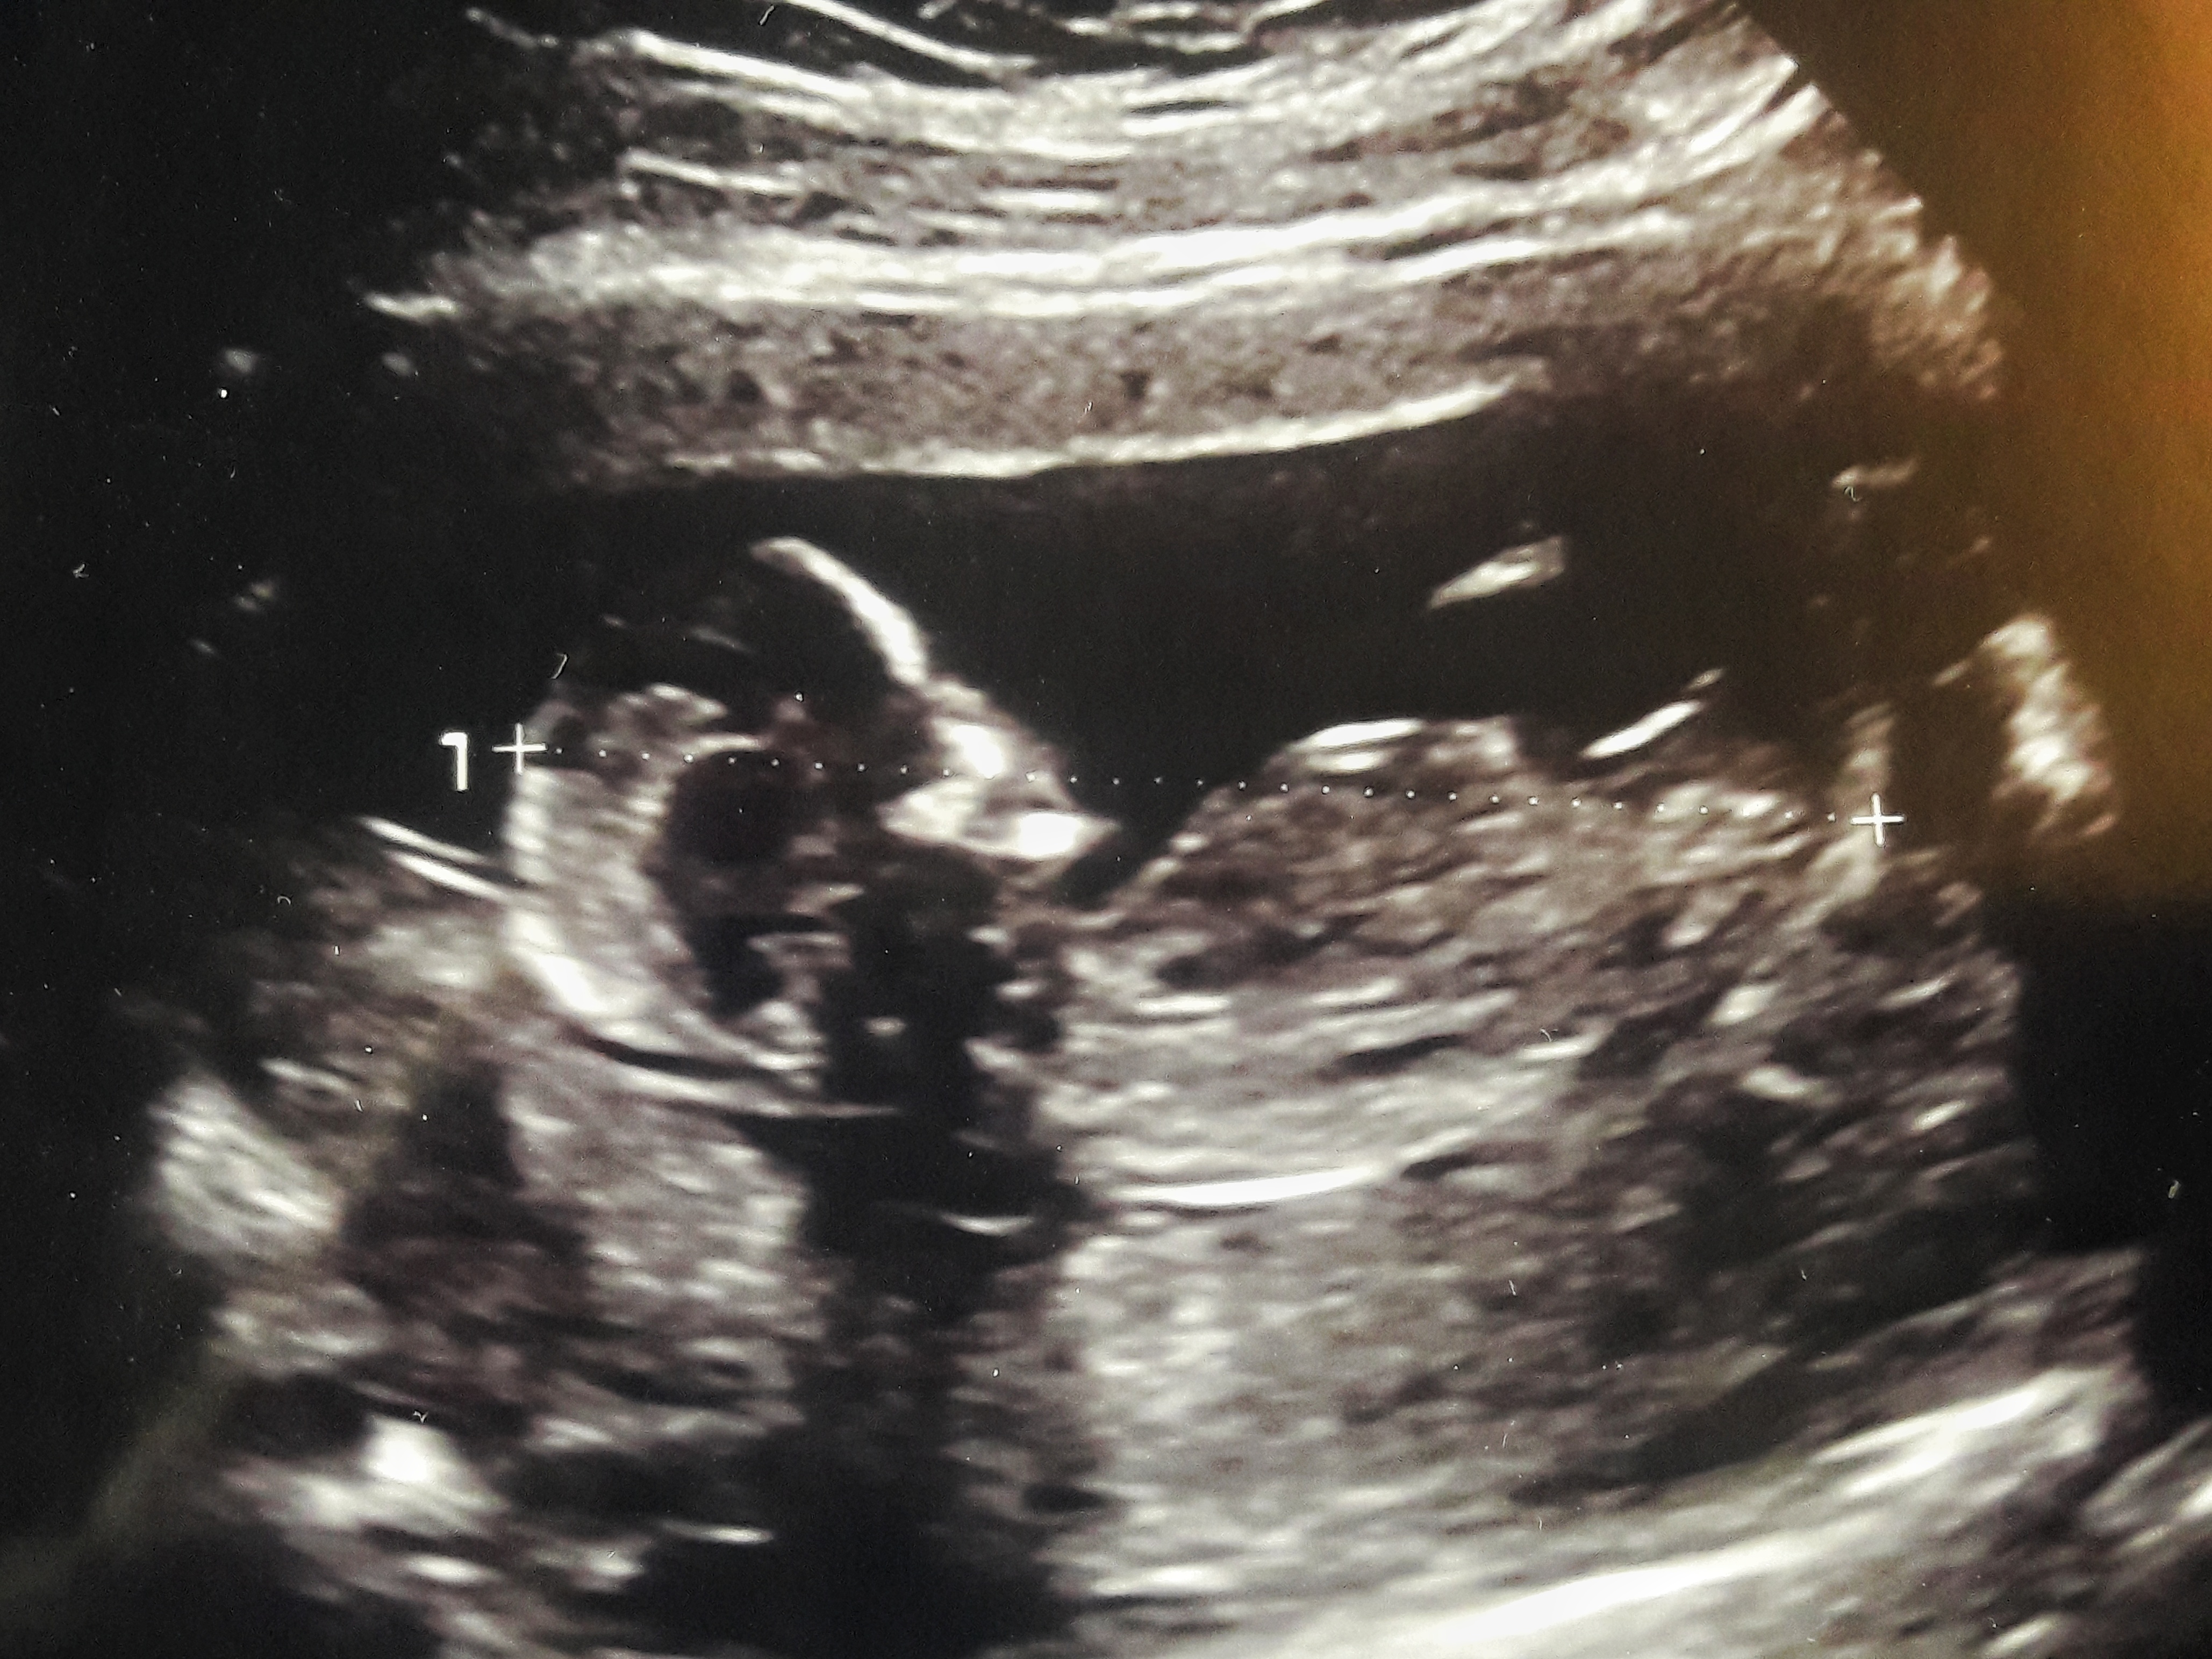

Zdravím. Nedávno jsem narazila na diskuzi ohledně ultrazvuku a poznání zda je na něm kluk ci holka. Do té doby jsem si říkala že je zo blbost poznat, ale tak prý tomu rozumím. Pokud je tam něco vidět, máte tip?

Obávám se, že na fotce postavy se to pozná dost těžko, to chce speciální záběr a nejlépe ještě v pokročilejším týdnu těhotenství...

3.12.2019 11:55S téhle fotky určitě ne, doktor je musí zaměřit mezi nožičky. Každopádně mě řekli první odhad v 16tt a pak už jen potvrzovali

3.12.2019 22:30Všechny ultrazvuk vypadají jak holky i když to je kluk že začátku. Tak je trebas počkat. Já věděla kluka už ve 14 týdnu a ve 14 týdnu věděla zase moje sestrenka holku a tak se i stalo, máme už roční deti